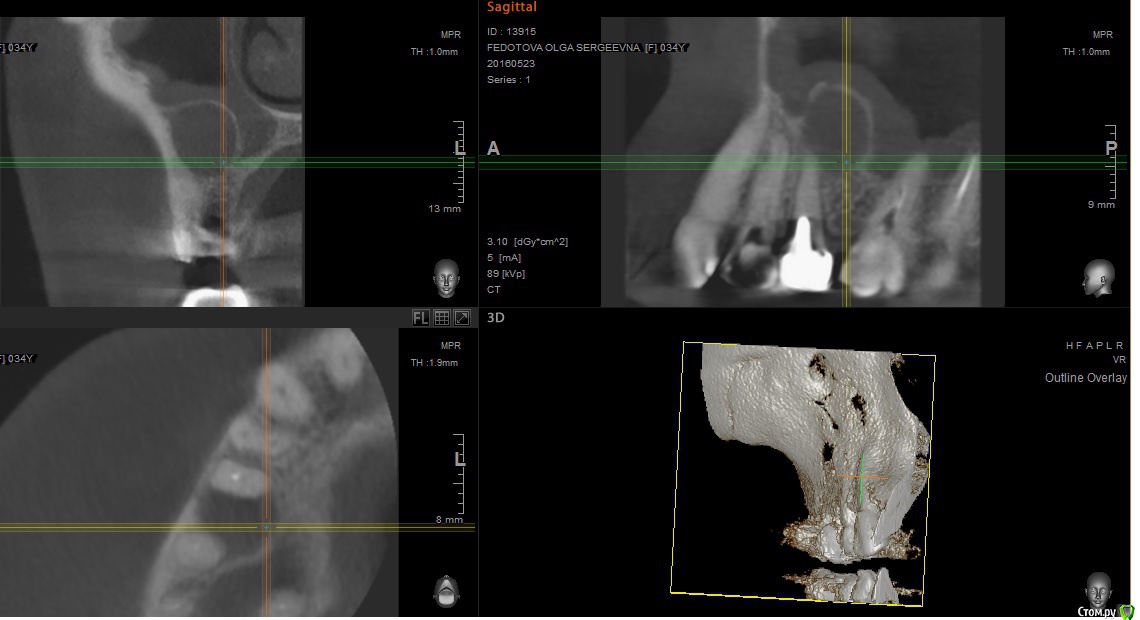

paciente Опубликовано 11 июня, 2016 Автор Поделиться Опубликовано 11 июня, 2016 Здравствуйте! Снова поднимаю тему.Начала перелечивание зубов под операцию. При перелечивании шестого зуба нашли обломок инструмента в канале, отправили к терапевту-микроскописту, вместе с ней решили попробовать консервативное лечение, до этого терапевты советовали только операцию.На данный момент перелечен четвертый зуб, пятый пока остался как есть, в шестом зубе перелечены три канала из четырех, все под временными пломбами.План доктора такой: 17-го июня постоянная пломбировка четвертого зуба, затем окончательное перелечивание шестого зуба и его постоянная пломбировка, как я поняла, одновременно, потом занимаемся пятым зубом. Смущает то, что хирурги говорили, что постоянная пломбировка делается в день операции, либо максимум за день. Подскажите, пожалуйста, правильна ли тактика врача в моем случае? Врач на мой вопрос ответила, что хирург не знает об имунном ответе и, если после временной пломбировки ничего не случилось, то и от постоянной тоже ничего не будет. Так ли это?Прикрепляю сканы свежего кт, оно сделано до перелечивания четвертого зуба под микроскопом.Спасибо большое за ответы! Ссылка на комментарий

paciente Опубликовано 11 июня, 2016 Автор Поделиться Опубликовано 11 июня, 2016 https://yadi.sk/d/vsNfYLs3sRjY9 Ссылка на комментарий

red_butler Опубликовано 12 июня, 2016 Поделиться Опубликовано 12 июня, 2016 покажите снимки после лечения Ссылка на комментарий

paciente Опубликовано 12 июня, 2016 Автор Поделиться Опубликовано 12 июня, 2016 Мне их не делали.Могу сделать, но в Москве буду только 14-го. Нужно сделать простой рентген снимок четвертого зуба? Шестой и пятый зубы сейчас в том же состоянии, что и на кт. После того, как было сделано кт, мне перелечивали только четвертый зуб, перелечивали повторно, т.к. последнего врача не устроила работа предыдущего. Ссылка на комментарий

red_butler Опубликовано 12 июня, 2016 Поделиться Опубликовано 12 июня, 2016 Смущает то, что хирурги говорили, что постоянная пломбировка делается в день операции, либо максимум за день.если эндо лечение будет успешным, то операция не потребуется Врач на мой вопрос ответила, что хирург не знает об имунном ответе и, если после временной пломбировки ничего не случилось, то и от постоянной тоже ничего не будет. Так ли это?нет, бывает по разному Ссылка на комментарий